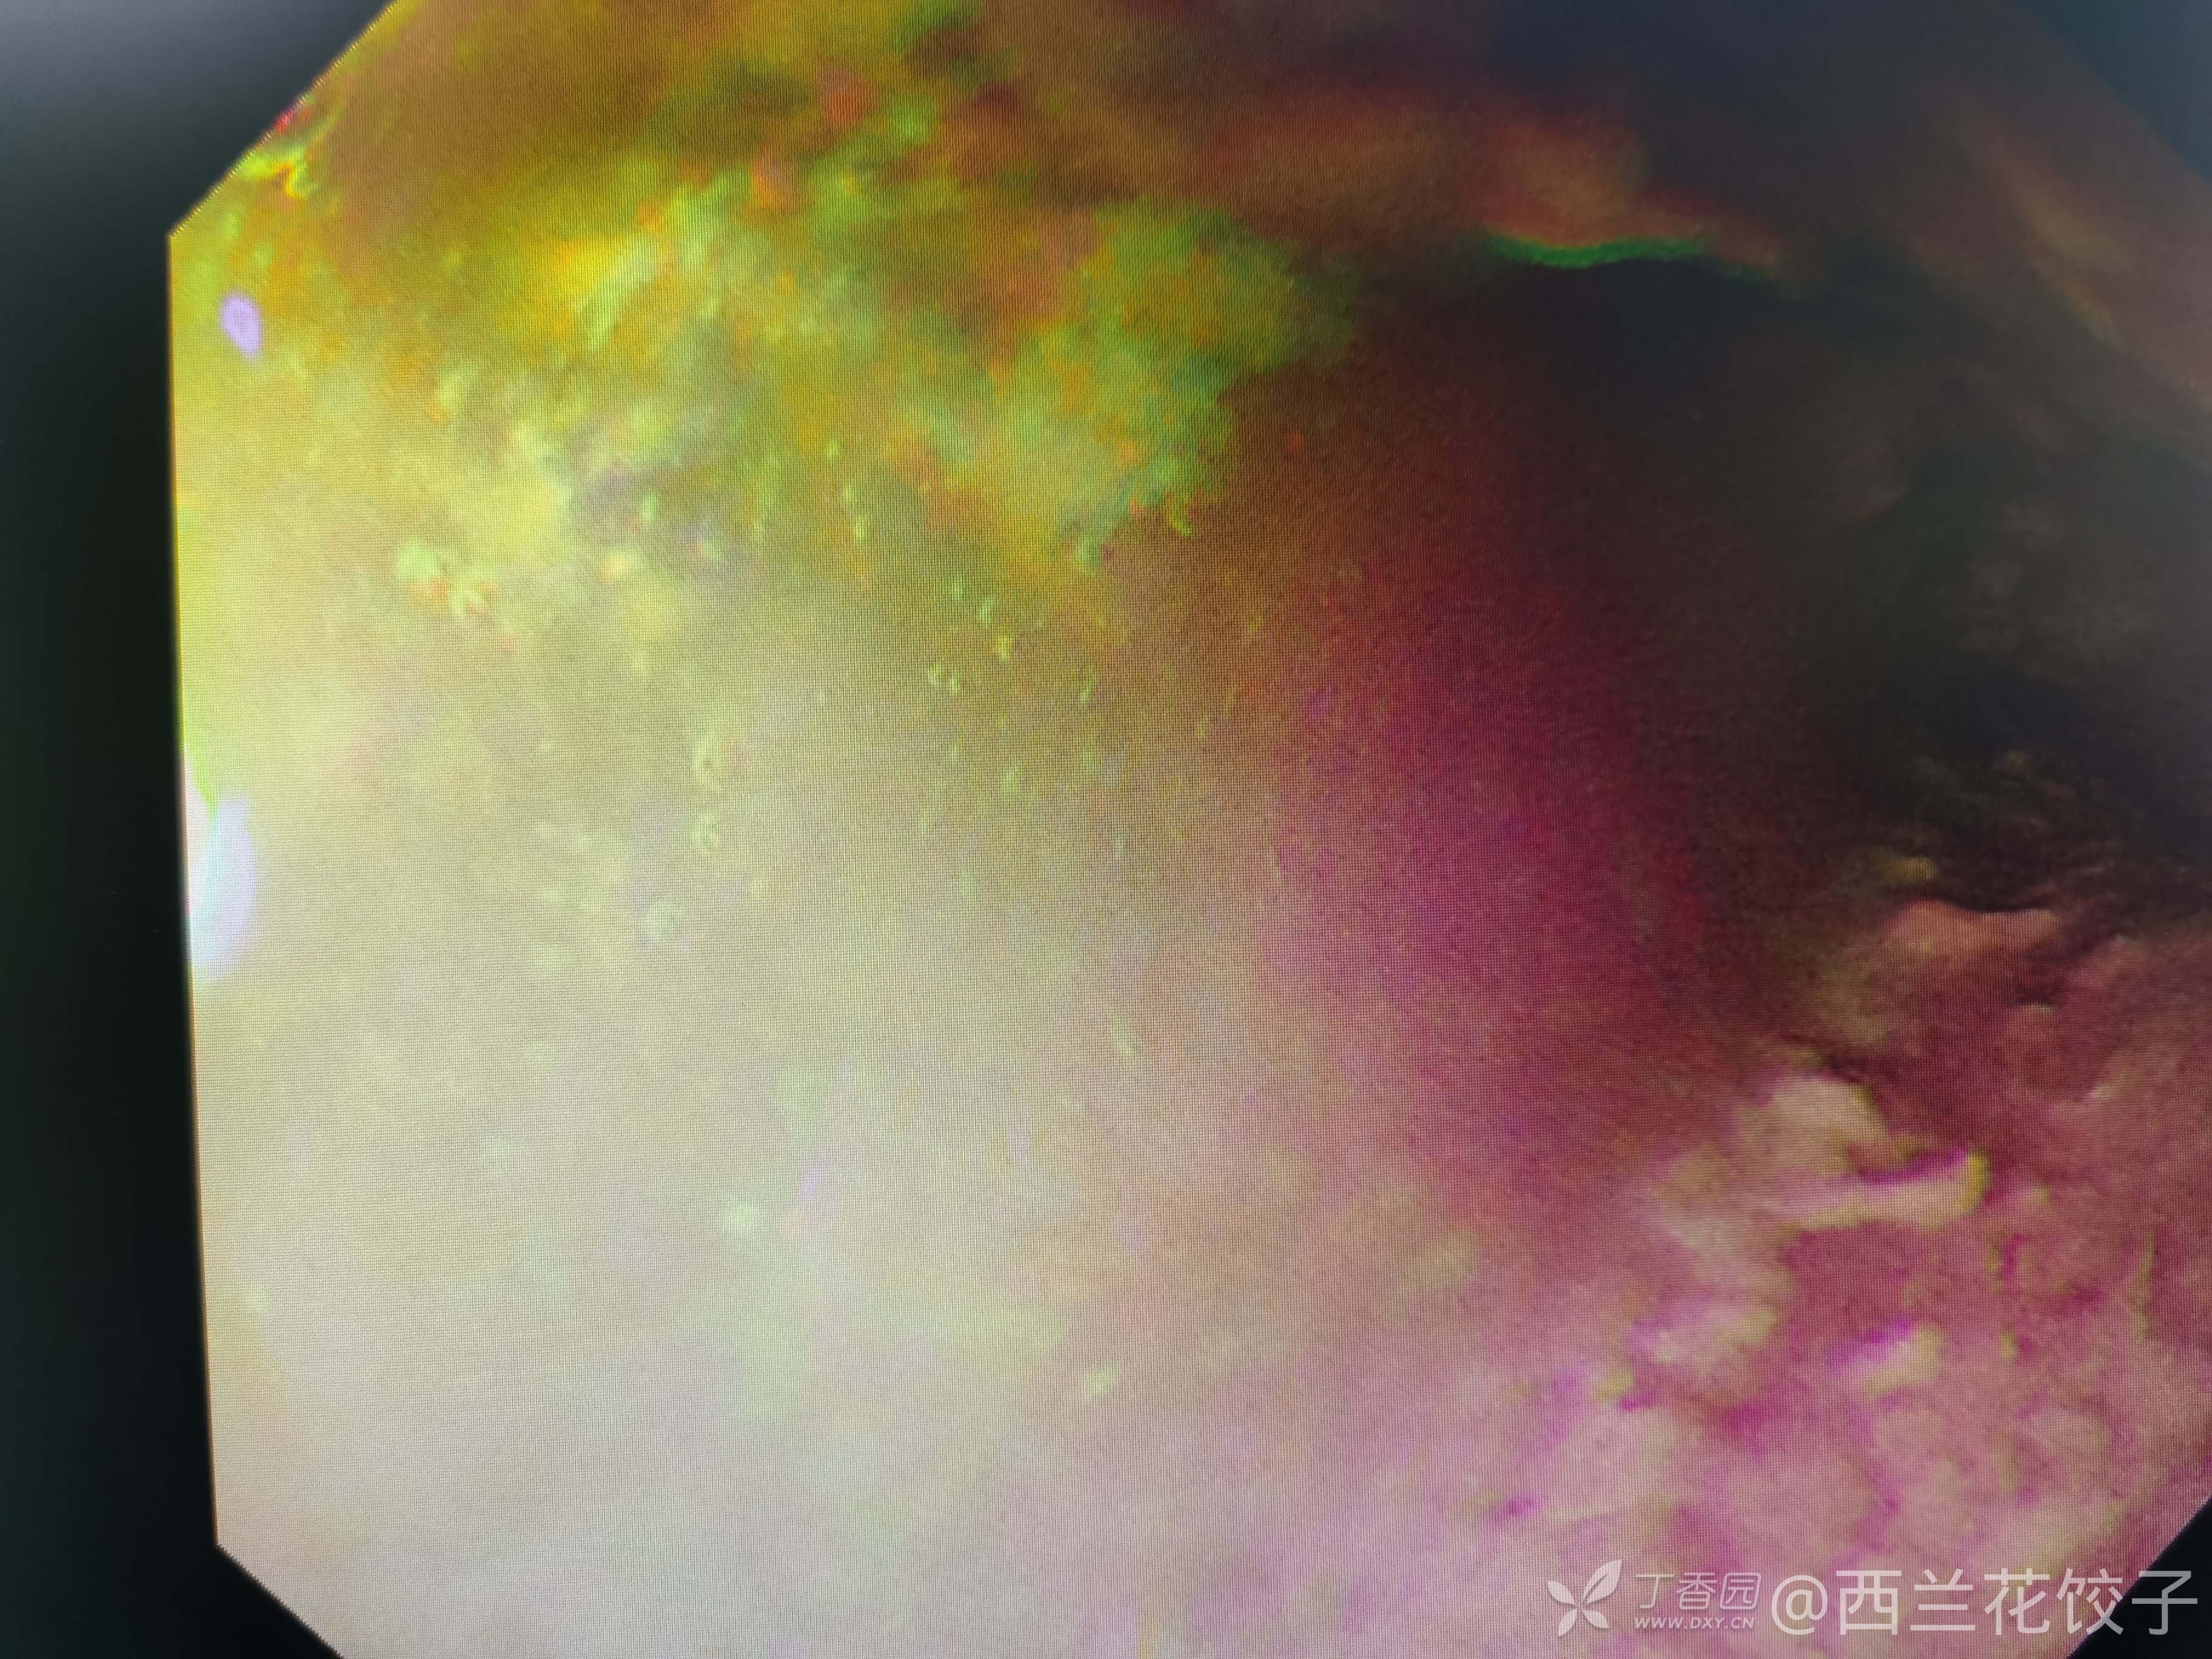

辅助检查:胃镜检查如下,食管内可见大量食物残渣及液体,胃腔内未见明显异常,胸腹部Ct如下,新冠核酸阴性。